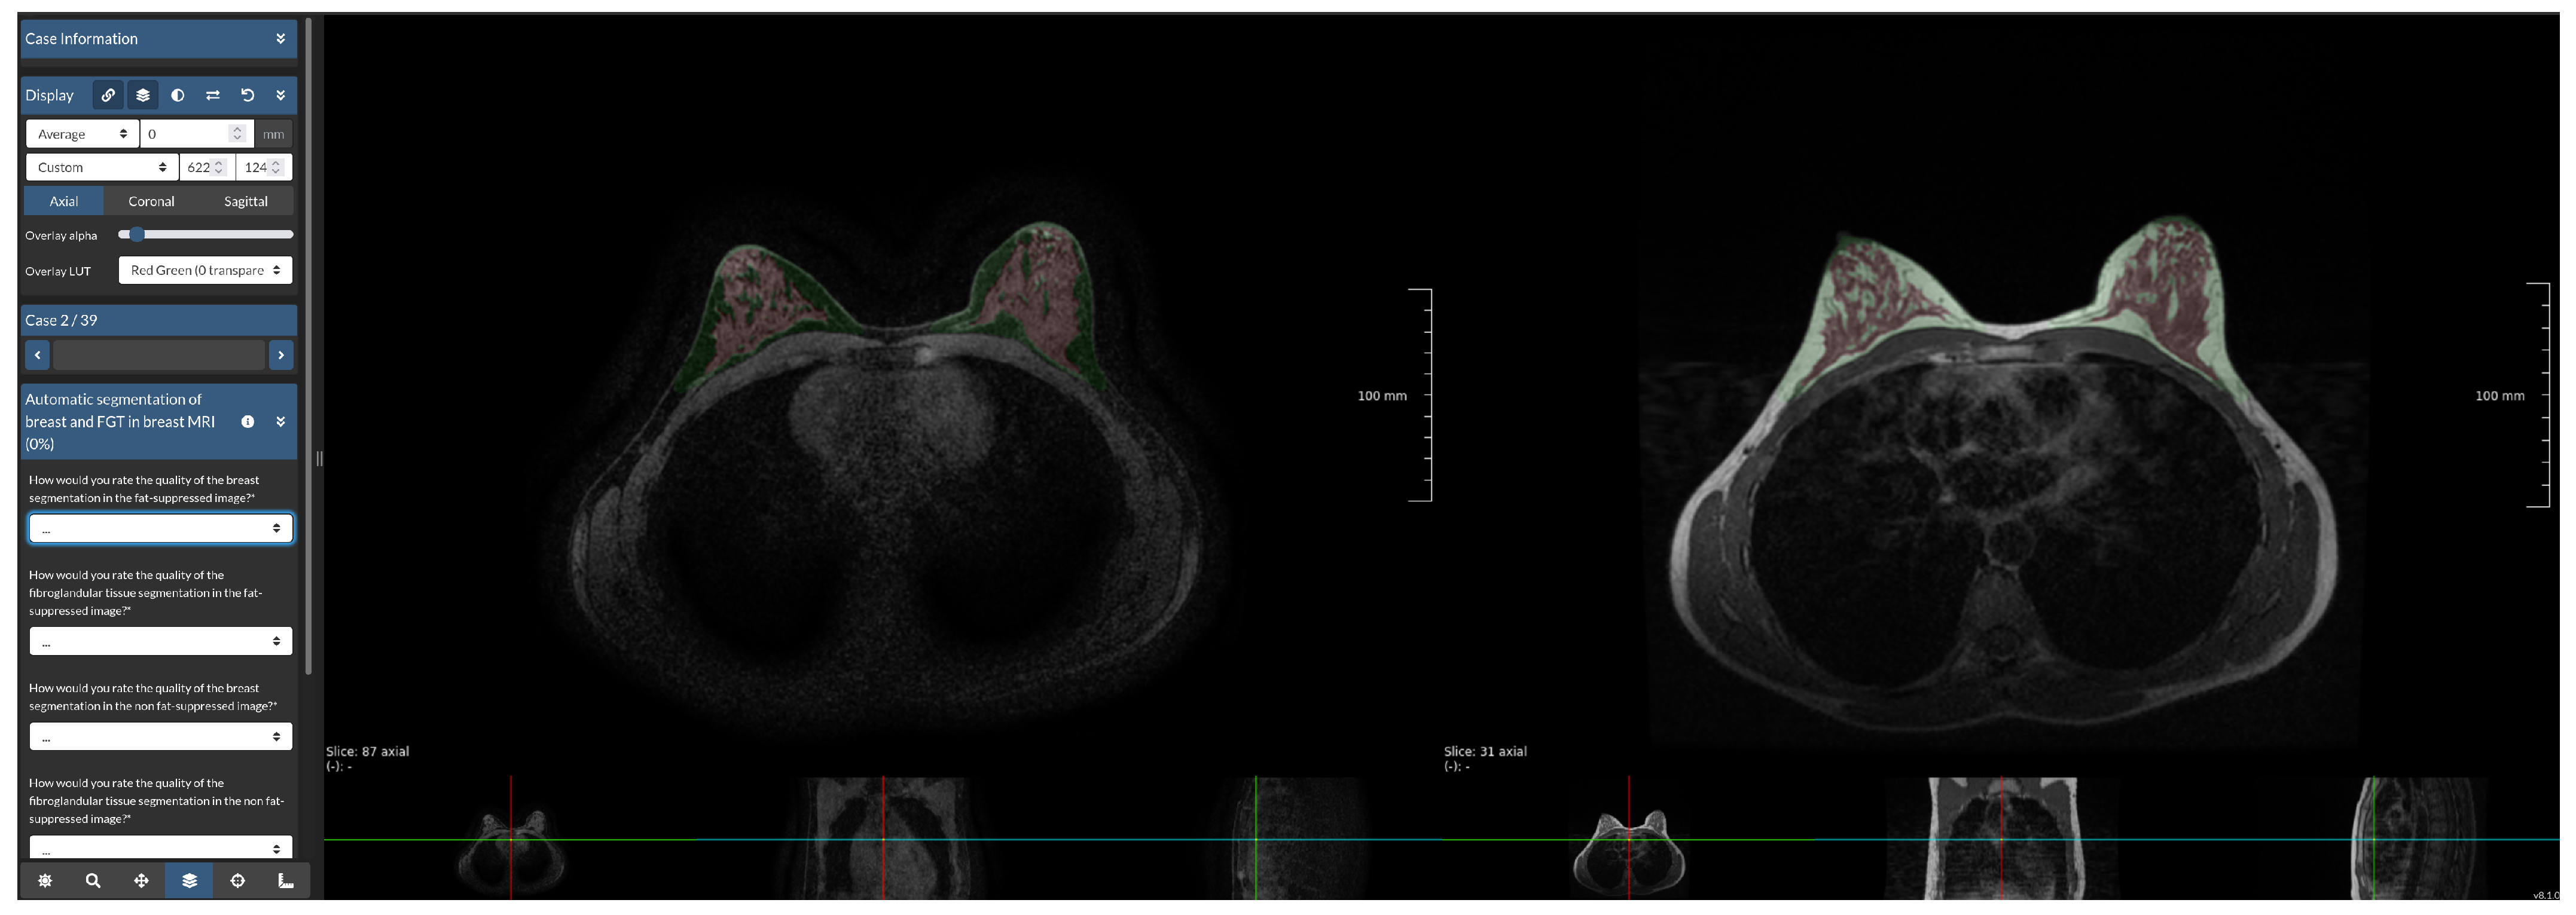

Figure 3. Screenshot of reader study set-up. The Grand Challenge platform allows the set-up of a web-based reader study with a fully functional medical imaging viewer. In this reader study, we showed participants the same WOFS and FS case side-by-side, and they were asked to answer the questions on the left side of the screen, which, in this case, were multiple choice questions.

We asked two breast radiologists (16 and 5 years of experience) to visually assess the quality of the breast and FGT segmentation produced by the network trained with WOFS + FS acquisitions. In Figure 3, an example of the reader study set-up is shown. For each case included in the reader study, we presented, side-by-side, both the FS and WOFS breast MRI acquisition with an overlay produced by the segmentation network for both acquisitions. The participant had the possibility to scroll through the volumes simultaneously and adjust the segmentation overlay transparency. The radiologist was asked to rate the quality of the breast and FGT segmentation both in the FS and WOFS versions of the acquisition for a total of four questions. The rating consisted of a four-point rating scale (1—Poor, 2—Fair, 3—Good, 4—Excellent). Additionally, the radiologist was asked to express a preference for the overall segmentation quality between the segmentation for the FS image and WOFS image, with the option of indicating no significant difference in quality. The order in which the cases were presented was randomized to account for a possible learning bias error, for every radiologist participating in the reader study. There was no restriction of time to finalize the reader study, and the radiologist had the possibility of partially completing the reader study before resuming from the point at which they left. Radiologists participating in the reader study had only access to the FS and WOFS acquisitions for each case, without any other clinical information.